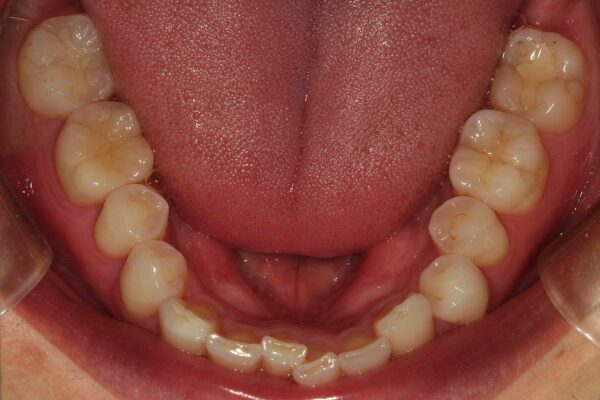

After

| 処置内容 | 欠けた部分から虫歯が進行していたため、根の治療を行い、土台を作り直し仮歯を装着。 その後、精密な型取りを行い、自然な色調再現性と適合性に優れたオールセラミッククラウンで最終補綴物を製作・装着しました。 |

| 患者さんの感想 | 食事のストレスがなくなり、たくさん食べることができるようになった。 |

| 費用 | オールセラミッククラウン:148,500円 抗菌性根充法(根管治療:66,000円 ファイバーコア(土台):22,000円 合計:236,500円 |